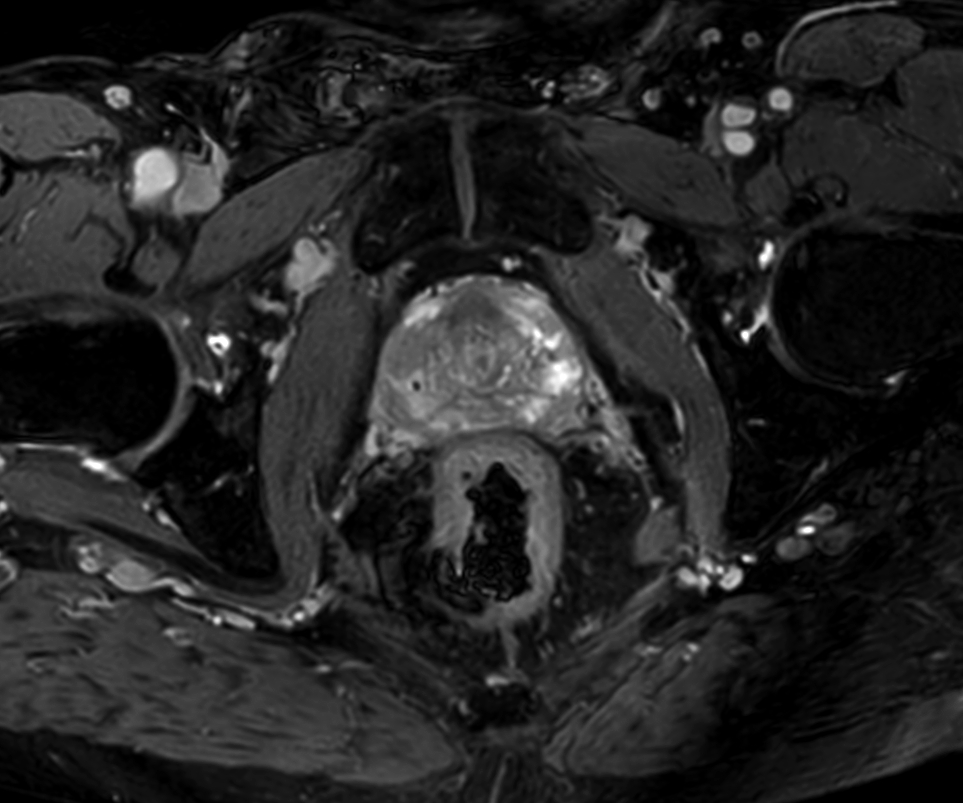

70-year-old male with prostate cancer, cT3bNxM, Gleason 6, PSA 7.9 mg/L, underwent MRI on Ingenia 3.0T MR-RT before radiation therapy, next to CT simulation. Patient was imaged at Ingenia MR-RT 3.0T using FlexCoverage Anterior Coil in combination with the integrated Posterior Coil.